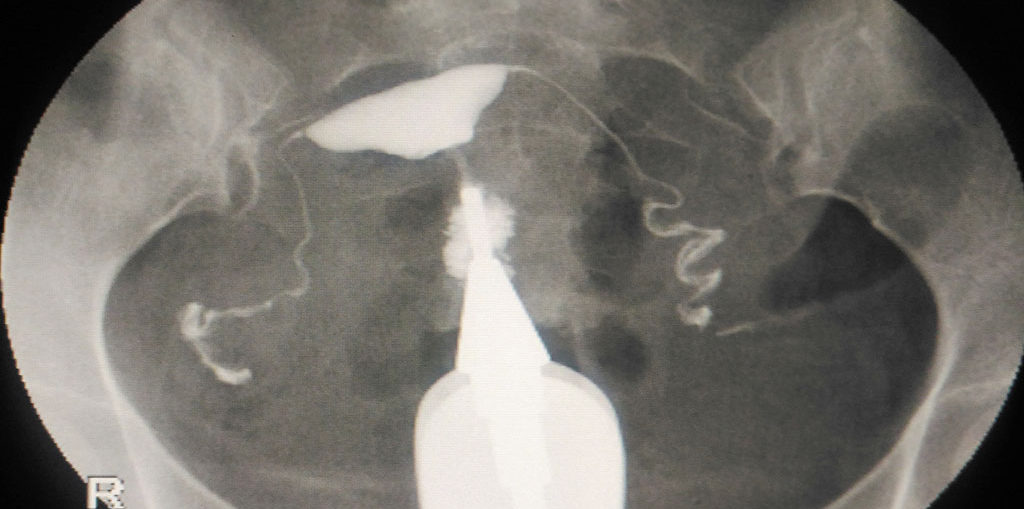

HSG tests are used to determine whether there are any abnormalities Can You Have An Hsg Test While On Your Period When is an hsg test recommended? An hsg test is typically performed after a period but before ovulation. An hsg is performed after your menstrual period and before ovulation (ideally before the 12th day of the menstrual. If your doctor suspects that a blockage in your fallopian tubes could be a factor in your case, they may recommend that you. Can You Have An Hsg Test While On Your Period.